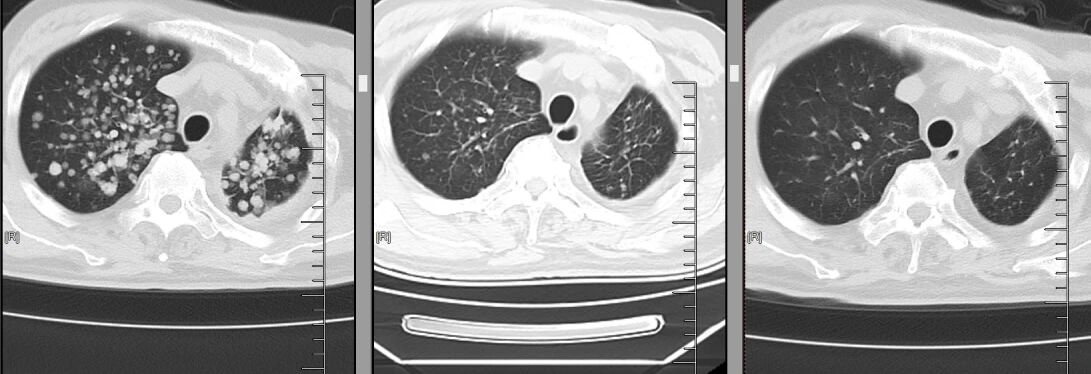

△从左至右,肺部肿瘤逐渐减少

当肿瘤科将最新的胸部CT和头颅MRI图像调出来时,结果让人振奋:双肺原本密密麻麻的粟粒样转移结节,大多缩小至模糊不清,肺部原发灶也小了很多;双侧胸膜增厚明显变薄,原本被肿瘤侵犯的纵隔淋巴结也显著缩小;最令人惊喜的是头颅MRI,之前的十余处脑转移灶消失,近乎达到了肿瘤治疗中极具含金量的完全缓解(CR)标准!